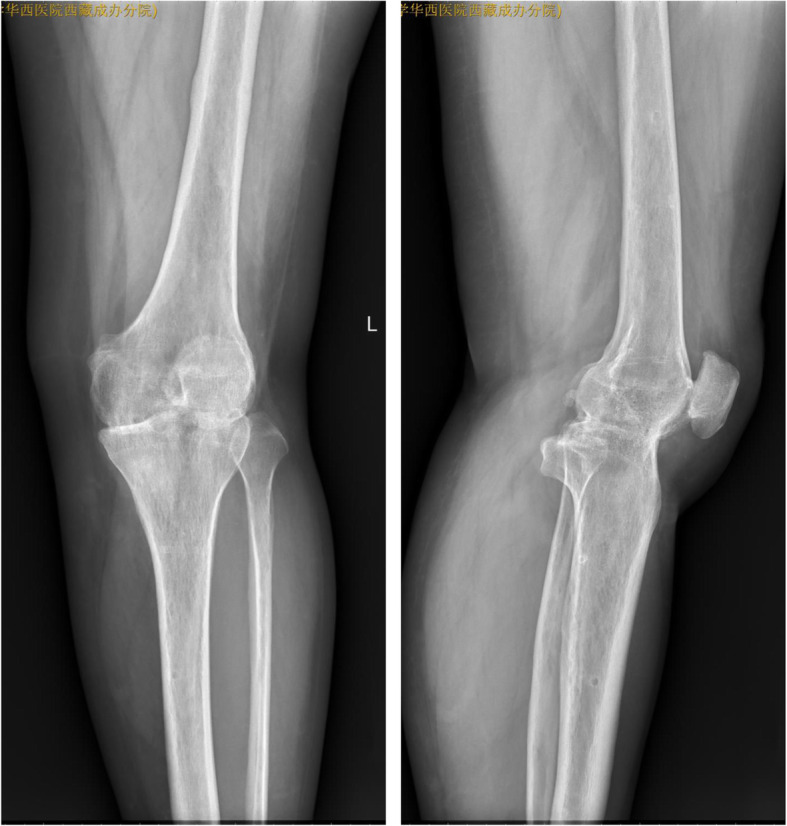

Fig. 6.

X-ray (anteroposterior and lateral): good knee fusion after removal of the external fixator (8.5 months after surgery)

Fig. 7.

X-ray (anteroposterior and lateral): successful knee joint fusion (26 months after operation)